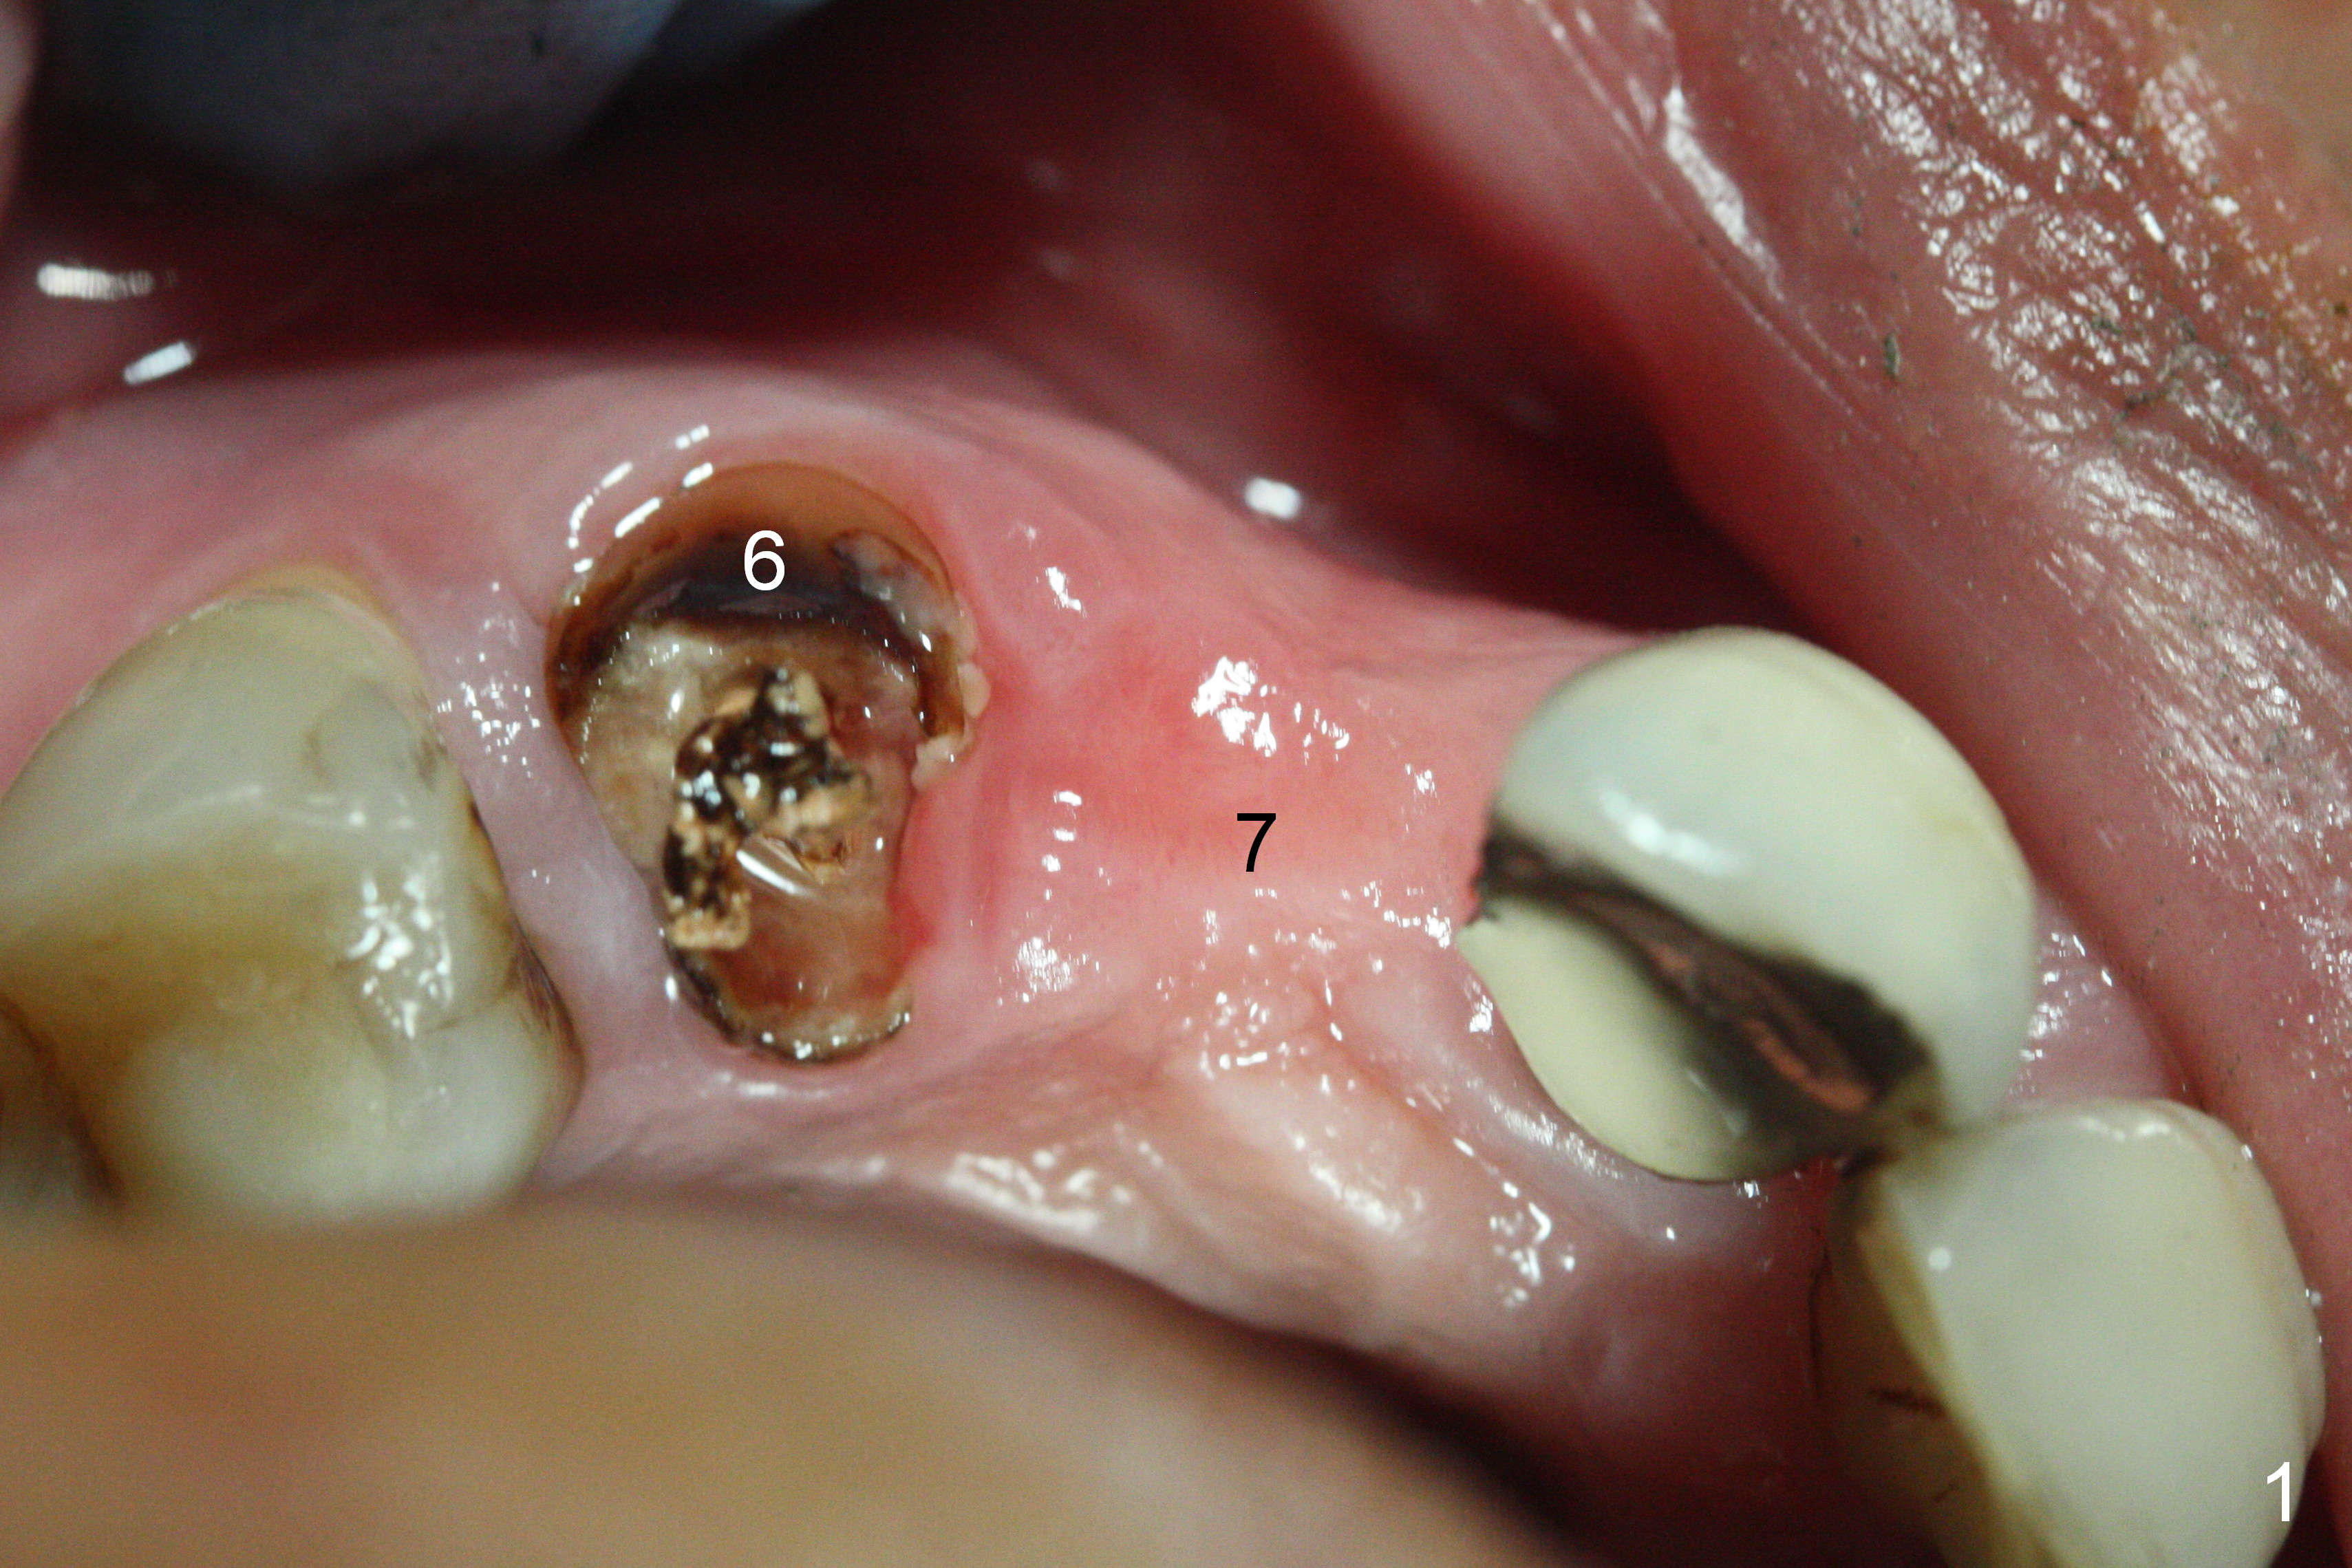

When the bridge is sectioned between #7 and 8, the tooth #6 is found non-salvageable (Fig.1). Incision shows the atrophic buccal plate at #7 (Fig.2 arrowheads); to prevent the same feature from happening at #6 with thin buccal plate, the most buccal portion of the root is preserved (socket shield (Fig.2-4: *)). The initial osteotomy is established in the palatal slope at #6 (Fig.5 circle) with 1.5 mm drill (Fig.6,7). A portion of the root is visible in Fig.6 (arrowheads). After sequential osteotomy with 2 mm, 3 mm (Fig.8) and 3.2 mm drills, a 4x15 mm implant is placed (Fig.10). To accommodate the cross bite, the coronal portion of the implant (Fig.9 white circle) is positioned close to the socket shield. It appears that the shield prevents the implant from encroaching the buccal plate.

Since the ridge at #7 is ~ 4 mm, a 2.5x14 mm 1-piece implant is placed (Fig.8) after 1.2 mm (Fig.7), and 1.5 mm drills at 12 mm and 2 mm drill at 8 mm. Later the implant is placed deeper (Fig.10). There is no bone loss 7 or 12 months postop, respectively (Fig.11,12). After Diode gingivectomy, there is papillary formation (Fig.13). No provisional is provided after impression (with the abutment torqued at #6) for oral hygiene. With access holes at #6 and 7, crowns are bonded with minimal residual cement (Fig.14 <, which is removed later). There is no hard (Fig.15,16) or soft (Fig.17 *) atrophy 26 months postop, i.e., 13 months post cementation, due to the presence of socket shield (Fig.15 <, as compared to Fig.1). In fact the tooth #8 has mobility and fremitus (short root/poor crown/root ratio, Fig.16); occlusal adjustment is done 13 months post cementation. The crown is dislodged 2 years 1 month post cementation; a prefabricated post is being tried in (Fig.18). There is no atrophy, bone loss or infection at #6 (with socket sheath (*)) or 7 two years 5 months post cementation (Fig.20-27).